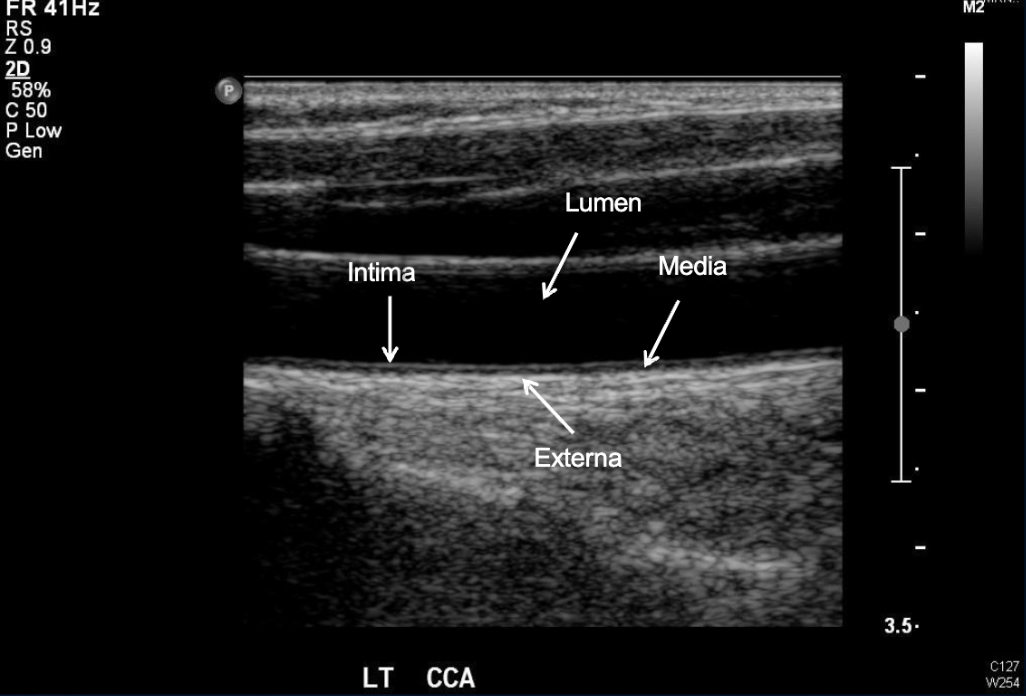

Label the anatomy of this Carotid Artery